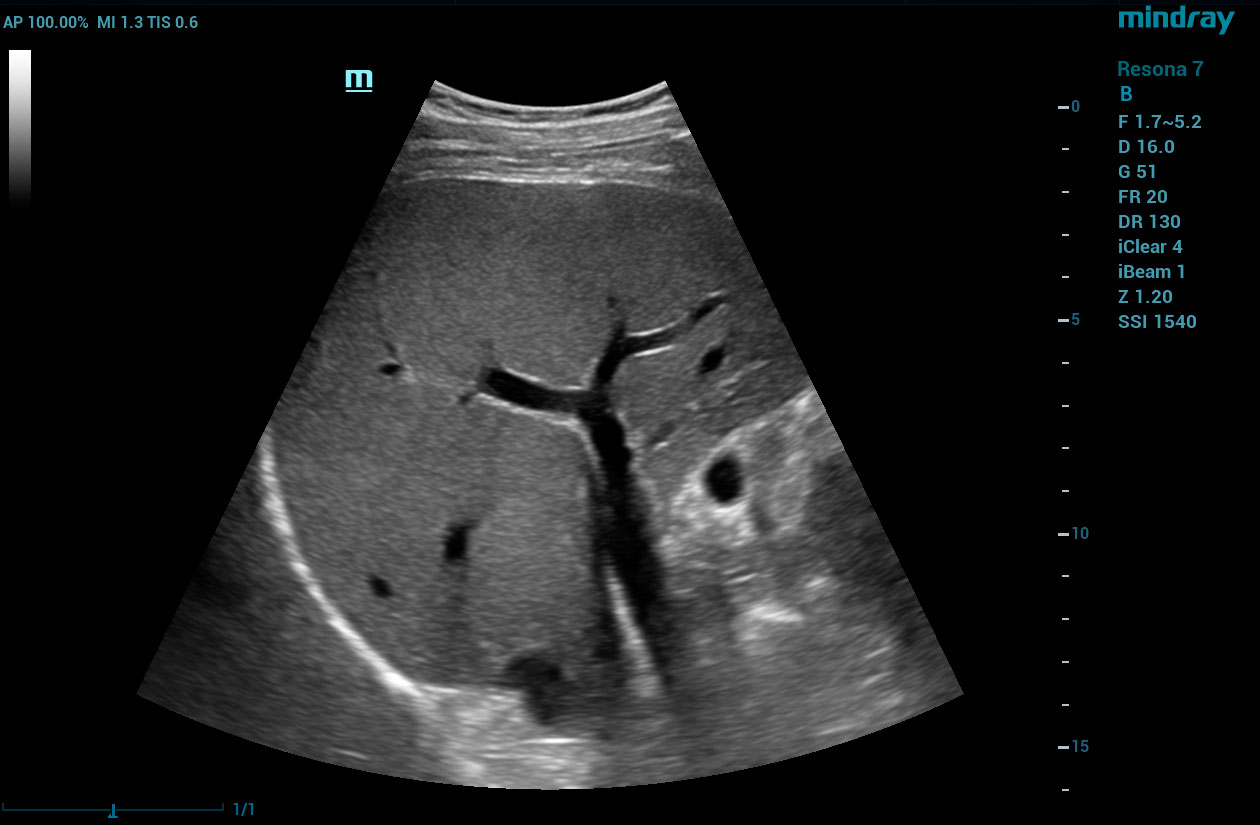

HD Scope

HD Scope is an advanced B-mode image processing technique that focuses additional imaging resources within a specified region of interest (ROI), analyzes the received channel data in unique ways, and applies various filtering and processing algorithms. This results in enhanced contrast resolution within the ROI based on the acoustic characteristics of varying tissue types.